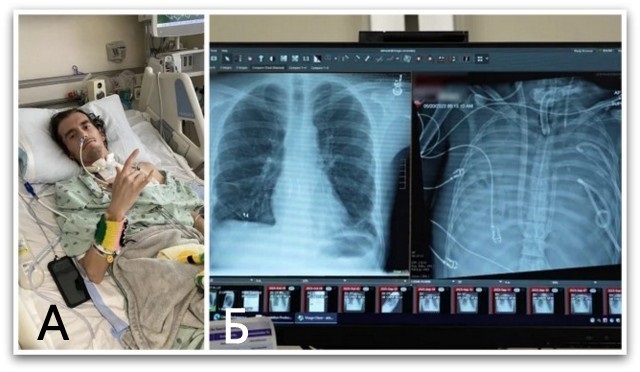

Белите дробови на Davey биле толку заразени што почнале да се претвораат во течност. При преглед на неговата рендгенска снимка не останало ништо – белите дробови биле целосно исполнети со гној, објасни др. Rade Tomić, пулмолог во споменатата болница.

Со младоста и добро здравје на негова страна, на Bauer привремено му ставиле импланти за градите на местото каде што му биле белите дробови. Еден ден подоцна, донаторски пар станал достапен, а на 28 мај, неговите нови бели дробови ги замениле имплантите. По неколку месеци закрепнување, Bauer не само што си го вратил здравјето, туку си доби и нов прекар “DD Davey”.